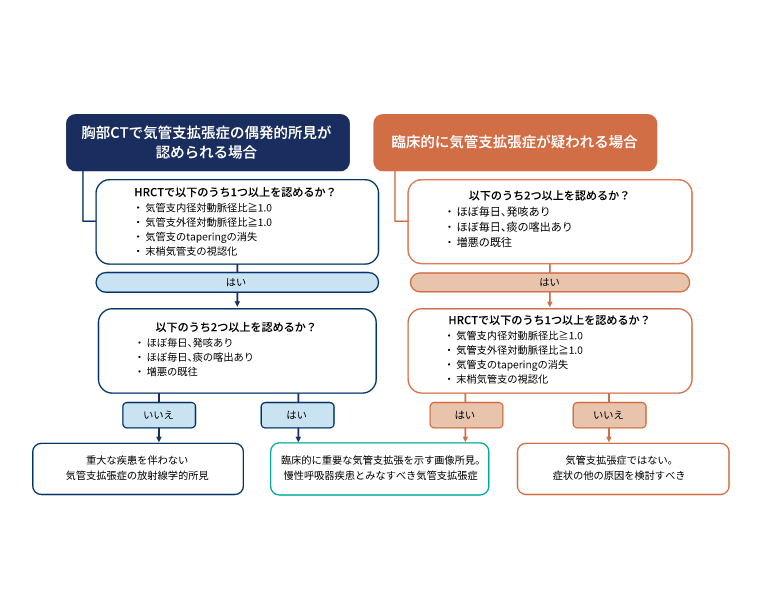

診断